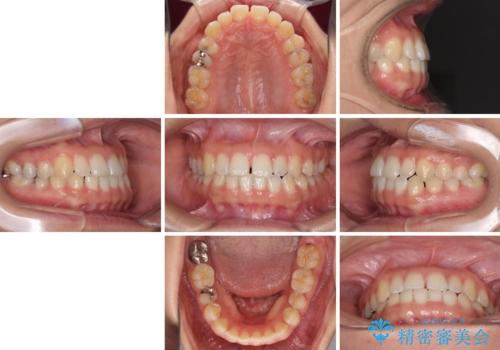

- 上の前歯の隙間を気にして来院された患者様です。

インビザラインの自己管理は自信がないとのことで、ワイヤー矯正により隙間を閉じていくこととしました。

下の前歯が上の前歯を突き上げるように咬合するため、咬み合わせの位置を改善しながら隙間を閉じていきました。

元々の歯並びが悪くなかったため、9ヶ月で綺麗に仕上がりました。